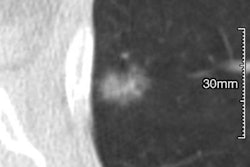

Reimbursement for lung cancer screening takes place under two codes: G0296 for the shared decision-making visit and G0297 for the low-dose CT screening exam itself. But the payment amount for the professional component is the same amount as for a diagnostic noncontrast CT scan (current procedural terminology [CPT] code 71250), despite the fact that extra work is required of physicians related to lung cancer screening, including registry participation and the use of Lung-RADS for reporting.